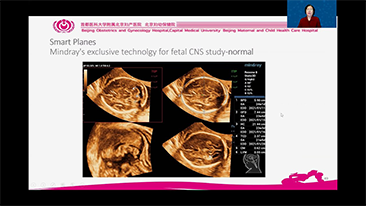

L'optimisation des flux de travail en gynÊcologie et obstÊtrique est indispensable pour traiter les volumes importants de patientes se prÊsentant pour des dÊpistages. Par exemple, les malformations du système nerveux central (SNC) font partie des anomalies congÊnitales les plus frÊquentes. Compte tenu des diffÊrentes conditions dans lesquelles sont rÊalisÊes les Êchographies, par exemple lorsque le f?tus est mal positionnÊ, il est particulièrement difficile de visualiser le plan transcÊrÊbelleux sur les Êchographies 2D. L'automatisation de la dÊtection et de la prise de mesures peut donc grandement amÊliorer l'efficacitÊ de l'imagerie.